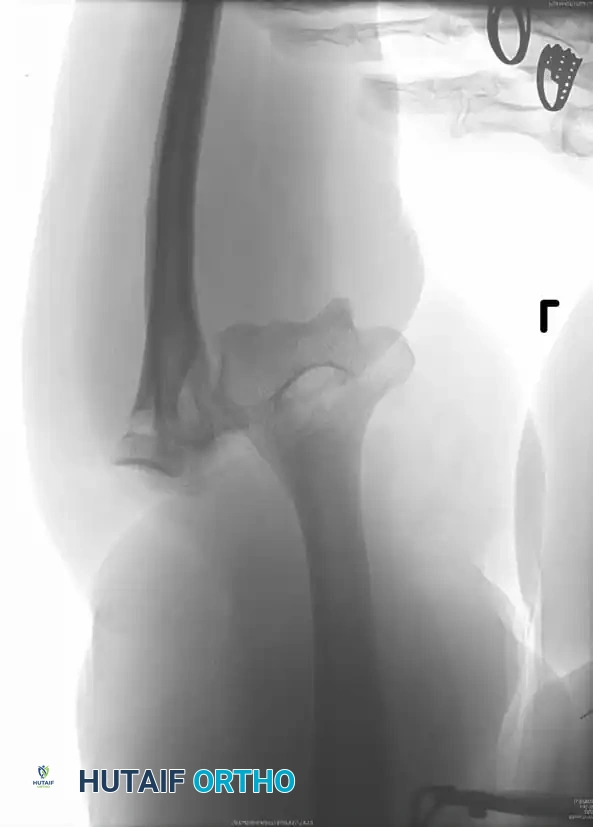

Associated Surgical & Radiographic Imaging